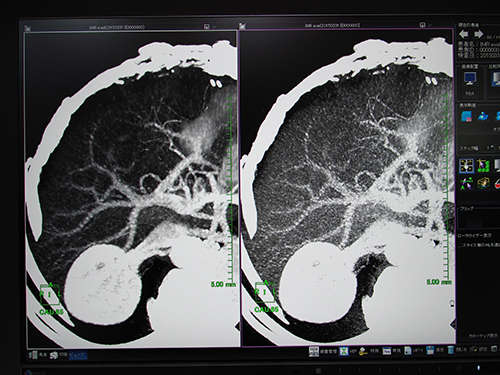

統計的CT画像ノイズ低減機能(W.I.P.)は,thin sliceのボリュームデータに適応した画像ノイズ低減機能。各ピクセルの三次元的近傍から推定されたノイズの統計量を基にノイズパターンを解析し,元の画像からノイズを差分することで画像ノイズの低減を行う。レトロスペクティブにノイズを低減できるため,thin slice画像再構成などの場合に生じる線量不足による画像ノイズを低減することができる。画像ノイズ(SD)測定では,線量を約1/4に低減しても同等の画質を得られるという。ノイズを低減することでコントラストが向上し,物体抽出の精度が上がるため,MIP画像やVR画像などで血管をより明瞭に描出することが可能になる。ワークステーションによる画像解析の精度は元画像のクオリティに依存するため,ノイズの少ない画像を得られることで,画像解析も容易になる。

レトロスペクティブにノイズを低減する統計的CT画像ノイズ低減機能(W.I.P.)

ノイズに埋もれた血管もノイズを低減することで観察可能

VR表示など,さまざまな表示法でノイズ低減効果が実感できる。